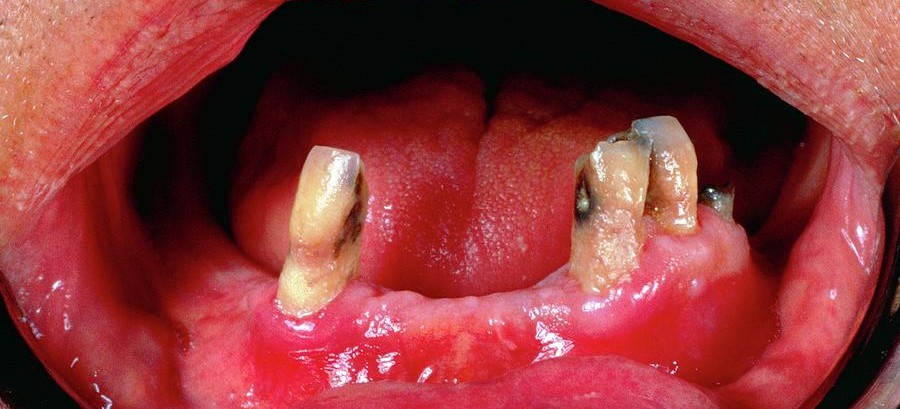

Os sinais bucais do escorbuto são frequentemente os primeiros a serem notados, tornando os cirurgiões-dentistas profissionais-chave na detecção precoce da doença.

A deficiência de vitamina C compromete a integridade dos tecidos periodontais, levando a diversas complicações:

Inflamação e sangramento na gengiva

A deficiência de colágeno enfraquece os tecidos gengivais, tornando-os propensos a inflamações severas.

Pacientes com escorbuto frequentemente apresentam gengivite intensa, com edema e sangramento espontâneo, mesmo na ausência de fatores locais irritantes.

Fraqueza dos dentes

A degradação do colágeno impacta os ligamentos periodontais responsáveis pela fixação dentária.

Com isso, os dentes podem apresentar mobilidade aumentada, elevando o risco de deslocamento e complicações associadas.

Perda de dentes

O avanço do escorbuto sem intervenção pode resultar na perda dentária progressiva.

A destruição dos tecidos de suporte e a fragilidade gengival levam à avulsão espontânea dos dentes, especialmente em casos crônicos.